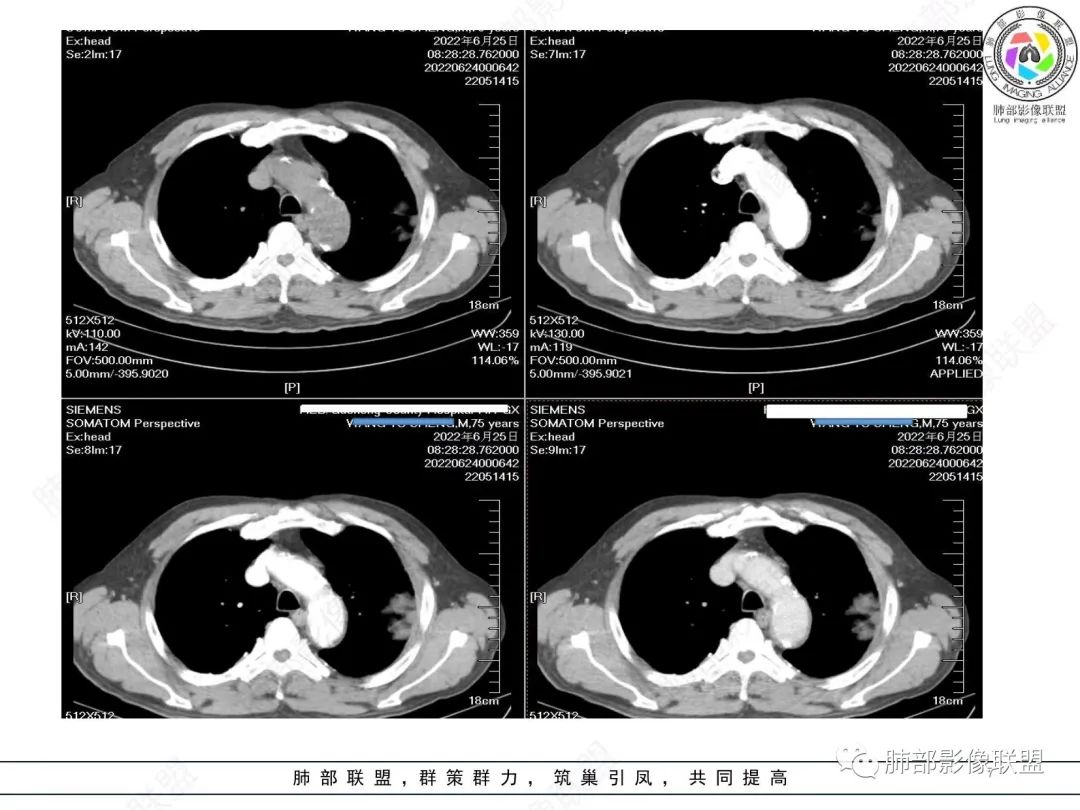

糖尿病史,慢性病程,左肺巨大肿块,跨叶生长,肿块近端可见充气支气管征及悬浮气泡,轻度圴匀强化,病变长轴与胸膜平行,炎性标志物正常,考虑放线菌,其次淋巴瘤

我要修正一下观点了:仔细看了视频,肿块占位效应明显,对周围血管,支气管有推挤,增强后强化不明显,NSE增高,半年体重下降25公斤,虽然有内部支气管扩张,血管漂浮,边界清楚支持淋巴瘤,但强化太低,膨隆,占位推挤太明显(淋巴瘤一般没有这么明显的占位效应),胸膜关系有载桩,恶病质明显(乏力,半年体重下降了25公斤),NSE也明显增高,就不支持淋巴瘤了。还是考虑外朝内的恶性肿瘤,间质来源的肉瘤伴有神经内分泌分化或者大神泌。

不支持淋巴瘤的有四点:1、对周围血管支气管推挤明显。2、胸膜有栽桩,3、强化太弱(淋巴瘤一般还是中度以上甚至高度强化多见),4、NSE升高明显,体重下降太明显。

腺癌一般不会有这么明显的推挤作用的。

淋巴瘤,鉴别间叶来源肿瘤或者神经内分泌肿瘤

支气管不像淋巴瘤,肺动脉走也不连续。支气管是断断续续的堵塞和扩张,狭窄。不是那种扩张

老年男性,糖尿病病史,消瘦、乏力三个月,肿瘤标志物高。左肺上叶胸膜下肿块,边界清晰,可见支气管影及坏死区,增强病灶边缘强化,内部未见明显强化,邻近胸膜有累及,考虑恶性,建议穿刺活检。

左肺紧贴胸膜巨大肿块,跨叶裂生长,密度均匀,边缘清晰,内支气管略扩张,增强见血管影,强化不明显,胸膜栽赃,钙化,考虑淋巴瘤。

我再建一下血管。支气管进入,但是近端推移,堵塞

大肿块,边缘光滑,深分叶

近端支气管堵塞、推移为主

部分类似于脐凹征

内部支气管扩张

肺动脉推移为主,边缘部分进入

淋巴瘤符合吗?